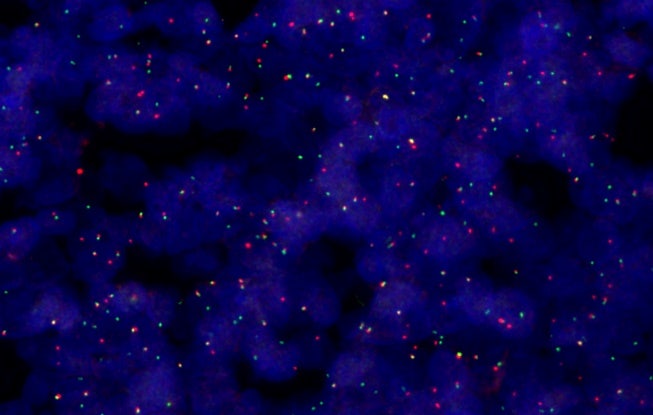

Analisi FISH, 40X

Supportando fino a sei obiettivi a alte prestazioni X Line™ e integrando un'illuminazione al LED True Color oltre a dei profili per fotocamera con colori corretti, il sistema SLIDEVIEW VS200 assicura chiarezza per le immagini di vetrini interi. Lo scanner è progettato per riprodurre in modo preciso le caratteristiche dei campioni e delle colorazioni, minimizzando la necessità di ripetizione di scansioni e supportando diagnosi efficienti.

Si possono scoprire più dettagli attraverso cinque modalità di imaging (campo chiaro, polarizzazione, fluorescenza, campo scuro e contrasto di fase) e la capacità di combinare diverse tecniche in una sola scansione. Questa flessibilità offre numerose possibilità di osservare campioni istologici e citologici, dalle analisi patologiche di routine alla complessa caratterizzazione molecolare di tessuti tumorali.